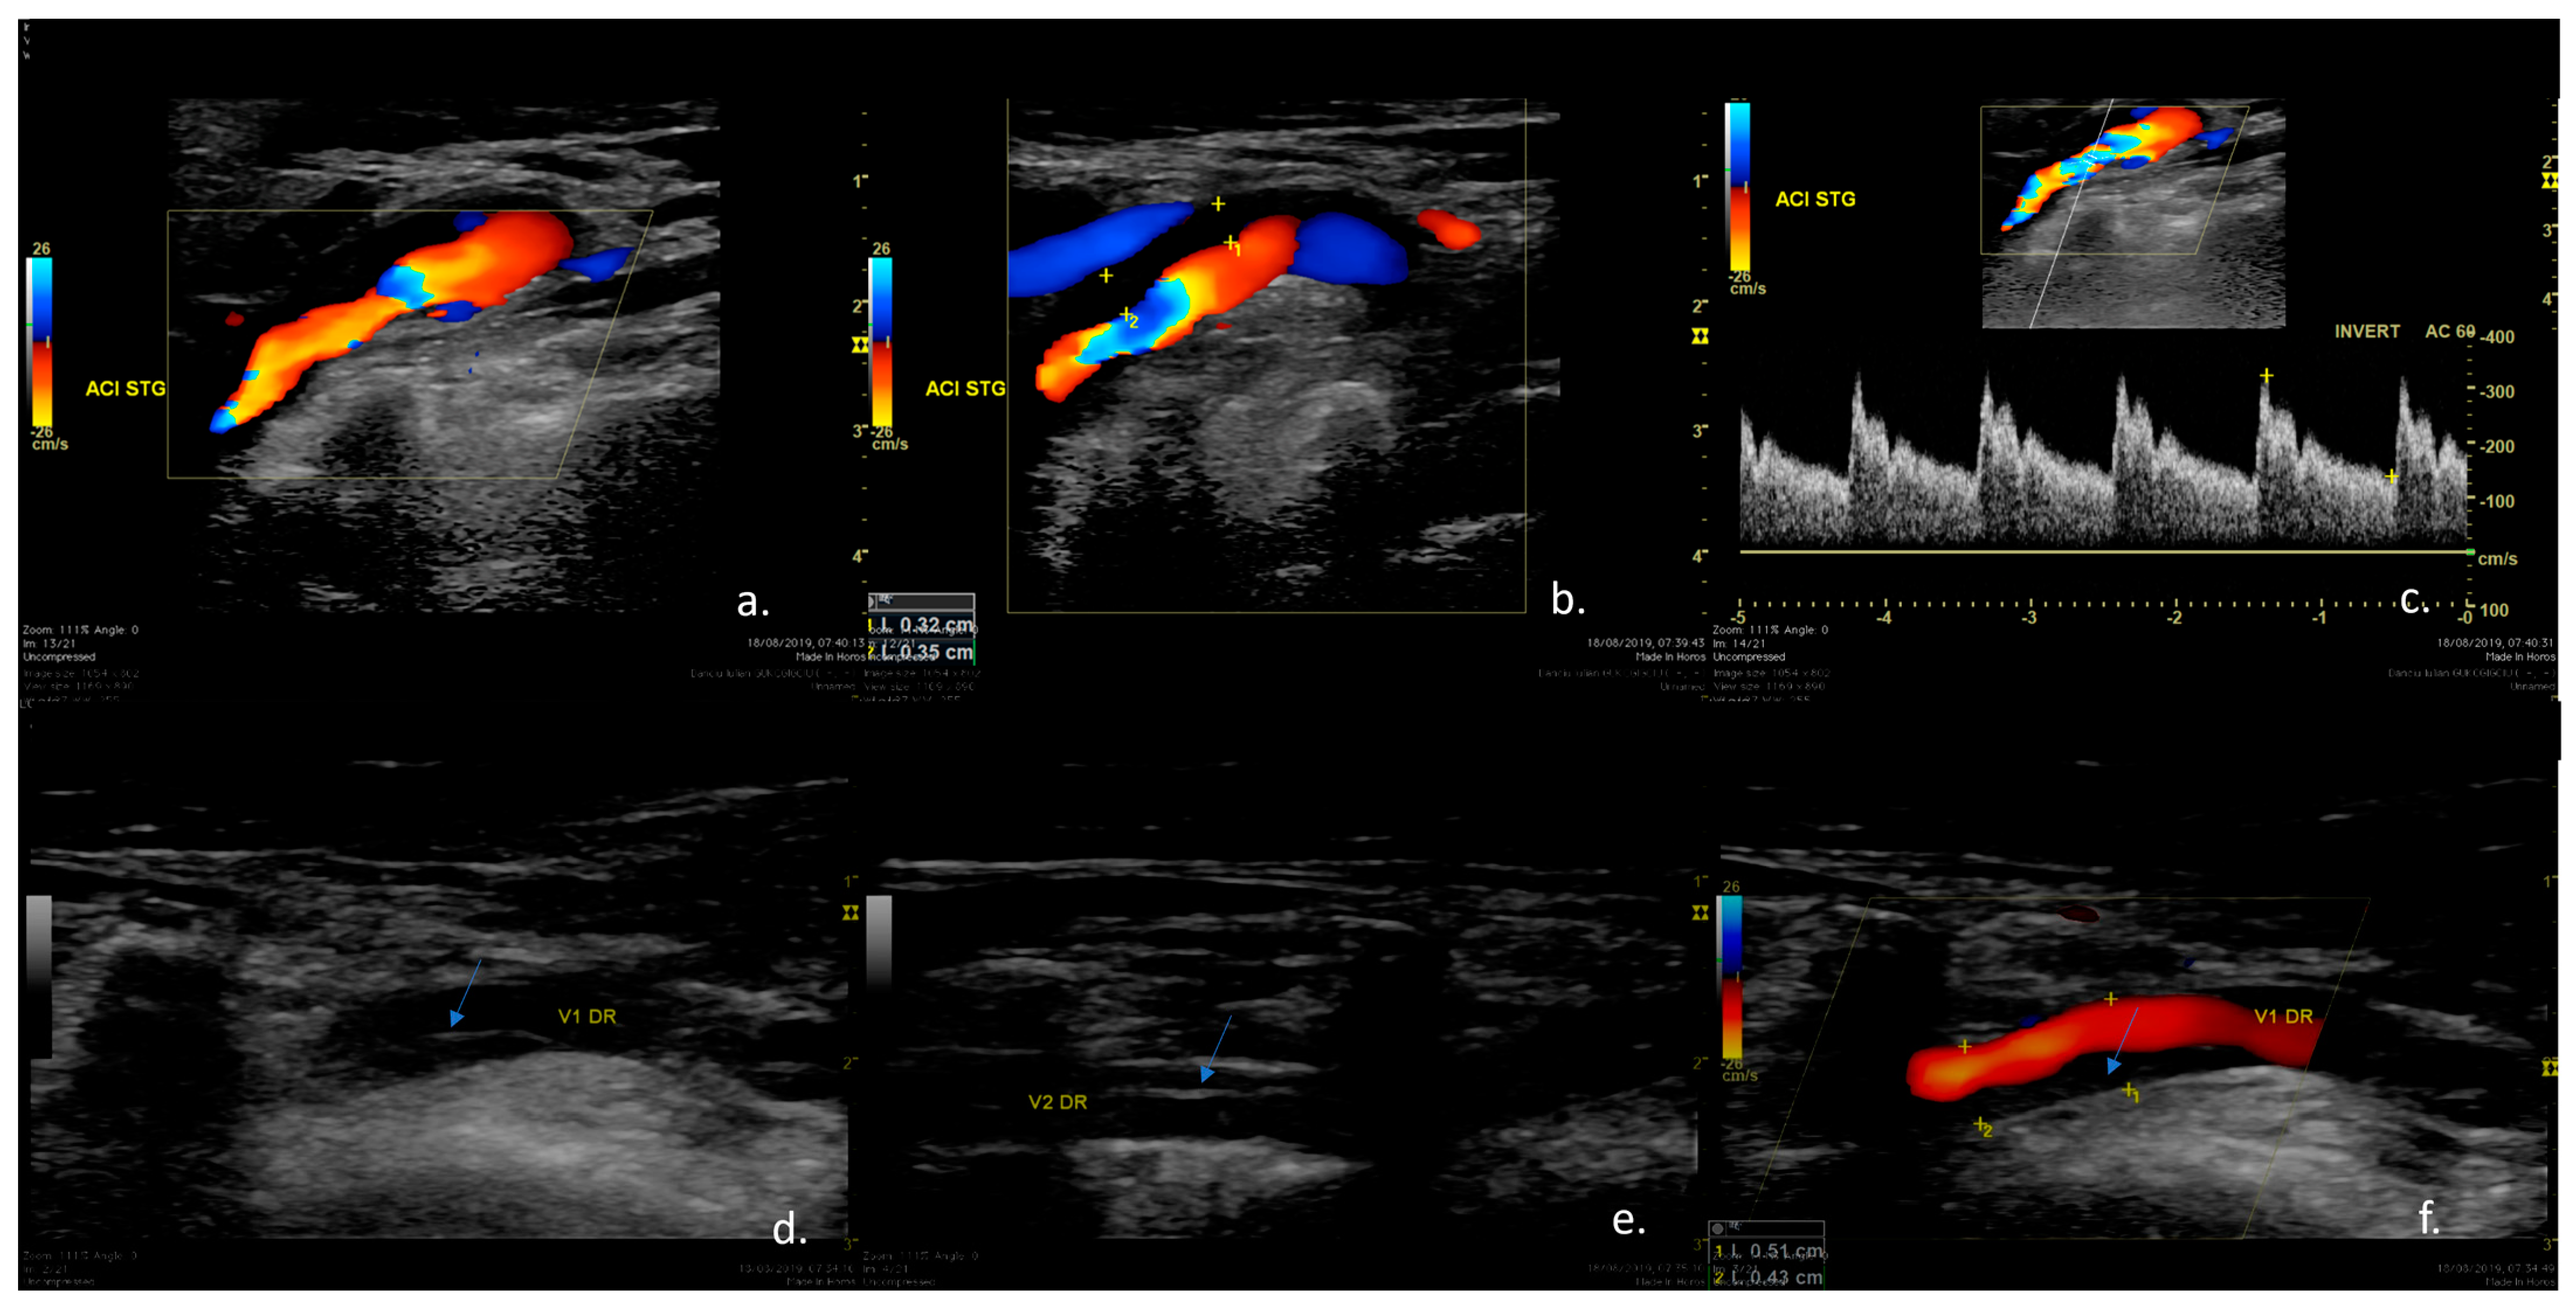

| Diagnosis tools that were used | ||

| Doppler Ultrasonography | 5 | 4 |